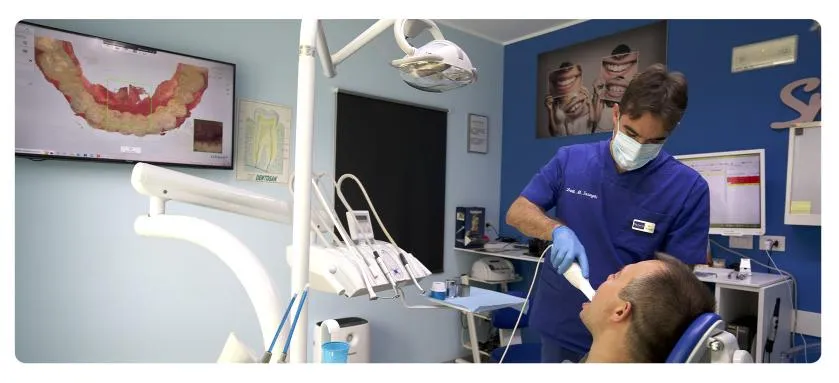

Fase 1. Raccolta delle aspettative del paziente e dei dati accurati, che comprendono fotografie dettagliate del volto e dei denti del paziente, radiografie e scansioni intraorali. Questi dati vengono poi caricati su un software specifico che analizza la posizione, la forma e la proporzione dei denti, il rapporto con le labbra e gli altri tratti del volto.

Fase 2. Match delle scansioni digitali della dentatura del paziente con foto frontali del paziente. Il medico a questo punto, attraverso il software, può creare una simulazione 3D del sorriso ideale e mostrarlo al paziente su monitor.

In questo panorama, realtà come lo studio del Dott. Michele Inzaghi a Settimo Milanese si distinguono come punto di riferimento rappresentando un esempio di come l'alta professionalità, l'aggiornamento costante sulle tecniche più innovative e un approccio profondamente personalizzato sul paziente possano convergere.